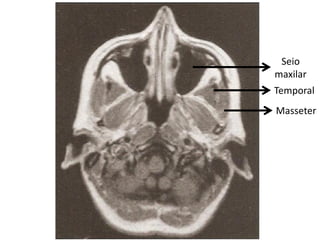

Temporal

• Fechamento

da mandíbula;

• Ato de apertar

os dentes.

Masseter

Seio

maxilar